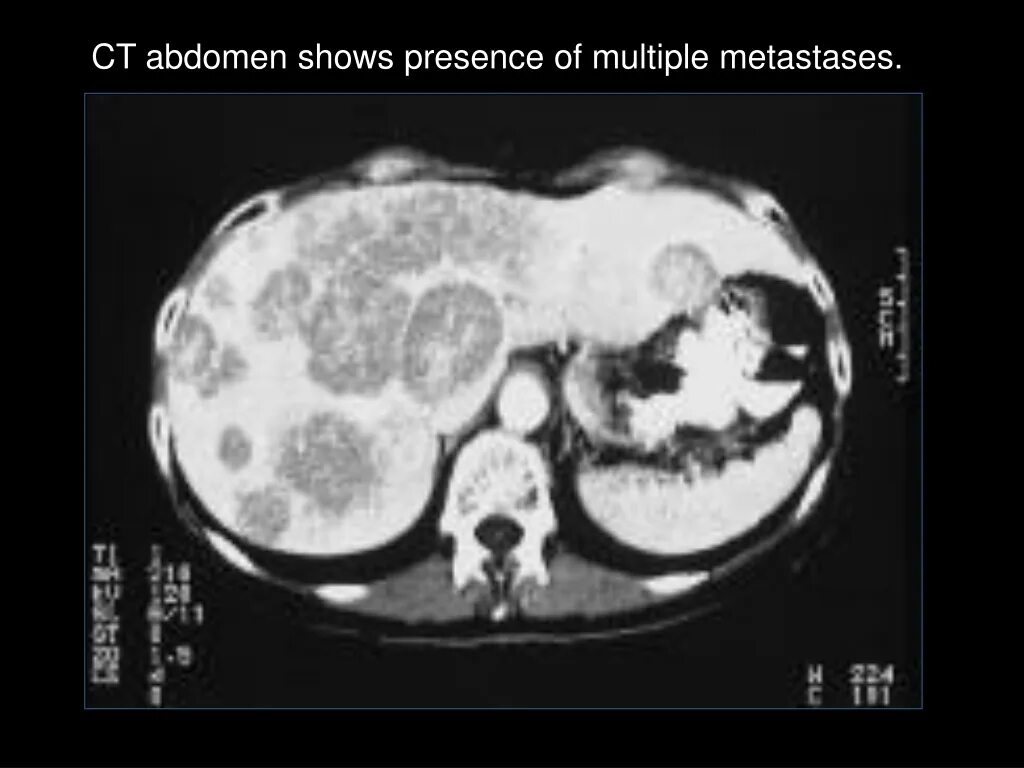

3 метастазы в печени